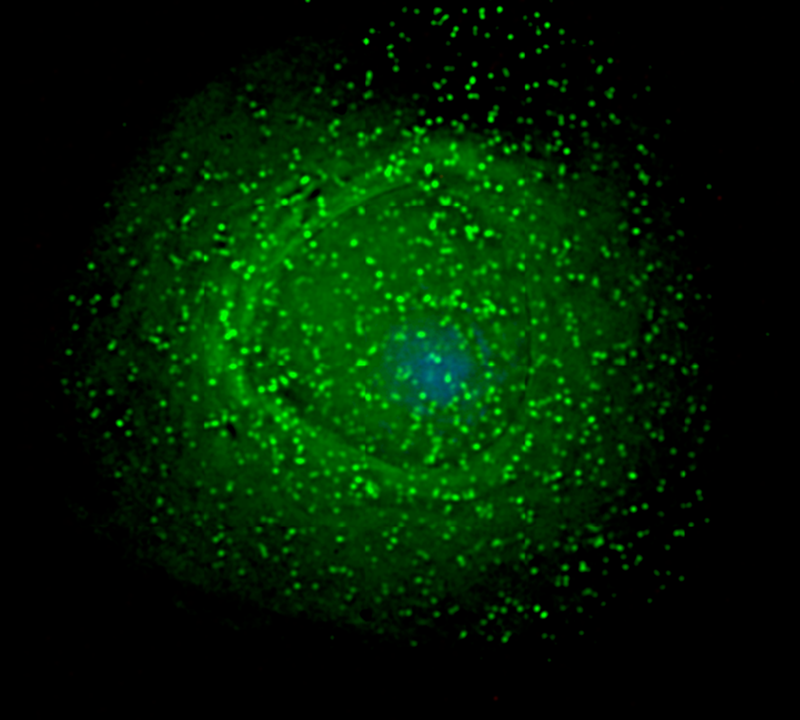

Em laboratório, a fotoimunoterapia conseguiu combater o vírus HIV

“O que nós fizemos foi uma combinação entre imunoterapia e terapia fotodinâmica. A terapia fotodinâmica é a combinação de luz e uma molécula que quando é irradiada pela luz essa molécula gera espécies reativas que oxidam a célula e matam a célula. É basicamente esse o princípio”, explicou Guimarães, um dos autores do estudo.

O pesquisador afirma que os anticorpos que carregam os fotossensibilizadores agem não apenas no vírus circulante, mas nas células infectadas pelo HIV. “Podemos utilizar essa terapia em conjunto com as drogas retrovirais, os coquetéis, que as pessoas HIV positivas tem que tomar para manter o vírus circulante no sangue zero. Quando se toma essas drogas, a gente basicamente elimina o vírus que está circulante no sangue, mas atua muito pouco nas células infectadas, que estão estocadas em algum lugar do nosso organismo”, disse.

Além disso, o pesquisador ressalta que um dos benefícios dessa terapia é que ela consegue atuar de forma direcionada ao vírus e às células infectadas. “O interessante é que [com essa terapia] eu só atuo no vírus e nas células infectadas, não vou afetar nenhuma outra parte do corpo senão as células que estão doentes e o vírus.”

Os testes em laboratório foram realizados com três mutações do vírus, que são predominantes na América do Norte, na Europa e no Brasil. Em todas as mutações, foi possível inativar o vírus por meio da fotoimunoterapia.